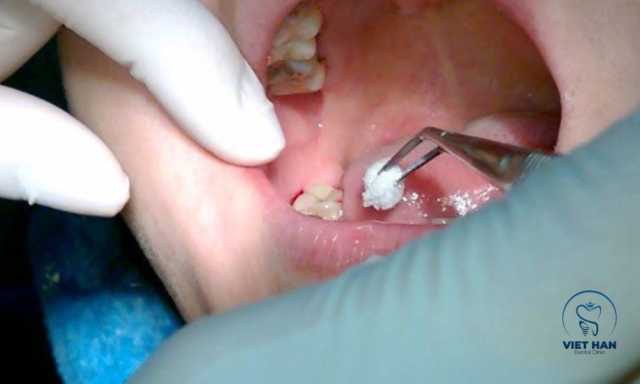

Công nghệ Piezotome sử dụng sóng siêu âm với đầu cắt siêu mỏng để bóc tách dây chằng nha chu và mô quanh chân răng một cách nhẹ nhàng. Nhờ tác động chính xác vào mô cứng mà hạn chế ảnh hưởng đến mạch máu và dây thần kinh lân cận. Nhổ răng khôn bằng công nghệ siêu âm có nhiều ưu điểm nổi bật như thời gian thực hiện nhanh, thao tác chính xác, giúp giảm đau, hạn chế sưng và chảy máu sau tiểu phẫu.

Nhổ răng khôn bằng máy siêu âm Piezotome với thao tác chính xác.

Tuy nhiên, kỹ thuật này có chi phí cao hơn so với phương pháp truyền thống. Phương pháp này không phù hợp với một số bệnh nhân sử dụng thiết bị y khoa đặc biệt như máy tạo nhịp tim và đòi hỏi bác sĩ có kinh nghiệm. Chính những lợi ích này khiến nhiều người lựa chọn công nghệ siêu âm để giảm lo lắng và tăng độ an toàn khi nhổ răng khôn.